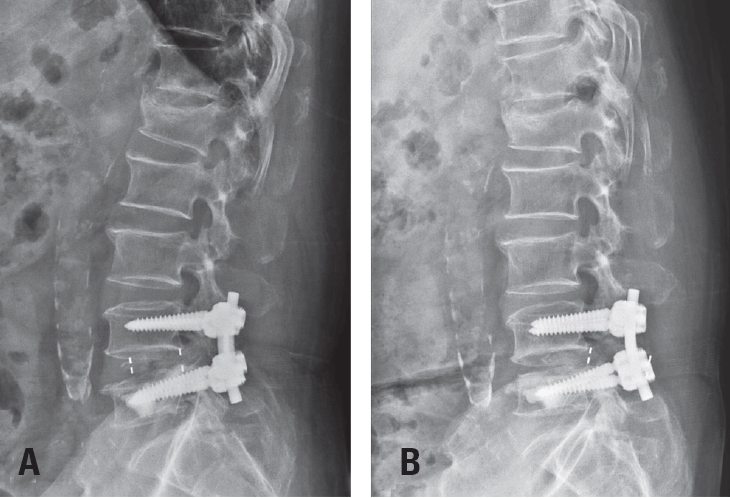

Postoperative imaging was essential for evaluating surgical outcomes. Standard radiographs and computed tomography (CT) scans were used to assess screw position and integrity. Mechanical failures—including pull-out and screw loosening—were identified by the appearance of a halo around the screw, indicating loss of fixation.10) Fig. 1 shows a typical pull-out, where the screw disengages from the vertebral body, whereas Fig. 2 demonstrates screw loosening, identified by the halo sign on CT imaging.

Fig. 3.

(A) Immediate postoperative radiograph showing pedicle screw and cage placement. (B) Follow-up radiograph at two months demonstrating cage protrusion, with the cage extending beyond the vertebral body margins.

Fig. 3. (A) Immediate postoperative radiograph showing pedicle screw and cage placement. (B) Follow-up radiograph at two months demonstrating cage protrusion, with the cage extending beyond the vertebral body margins.